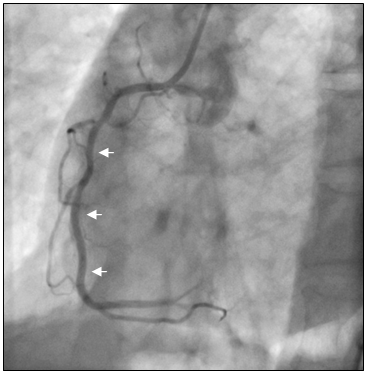

Bệnh nhân được chẩn đoán nhồi máu cơ tim cấp vùng hoành giờ thứ 2, Block A-V độ 3, có chỉ định chụp mạch vành cấp cứu. Bệnh nhân được kích nhịp bằng Atropin, Dopamin và truyền dịch chống choáng trên đường chuyển đến phòng thông tim. Kết quả chụp mạch vành cho thấy hẹp 90% ở đoạn xa RCAI (hình 6a), tuy nhiên khi chuyển sang góc chụp kế tiếp chúng tôi phát hiện thêm một chổ hẹp thứ hai rất nặng ở đoạn gần RCAI tại vị trí sát ngay đầu ống thông can thiệp (hình 6b). Nghi ngờ tổn thương do co thắt nên chúng tôi bơm 200µg Nitroglycerin vào RCA và chụp lại sau 2 phút. Kết quả chổ hẹp nặng ngay sát đầu ống thông can thiệp đã hoàn toàn biến mất (hình 7b), chổ hẹp đầu tiên ở đoạn xa RCAI chỉ còn 30% (hình 7a). Như vậy, nhồi máu cơ tim vùng hoành là do co thắt RCA tại vị trí mãng xơ vữa.

Hình 6: Tổn thương hẹp nặng RCAI nghi do co thắt mạch vành

Hình 7: (A) Hẹp 30% đoạn xa RCAI

(B) Không còn chỗ hẹp gần đầu Guiding